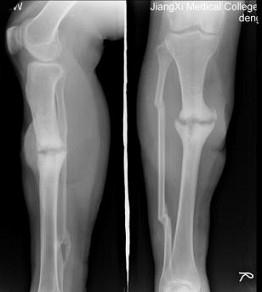

问题 48岁女性患者,因车祸致右胫腓骨骨折,行外固定术后两年复查,如图所示,最可能的诊断是 ( )

选项 A、右胫骨断端不连接 B、右胫骨畸形愈合 C、右胫骨假关节形成 D、右胫骨骨折愈合好,有大量骨痂形成 E、右胫骨愈合延迟

答案 A